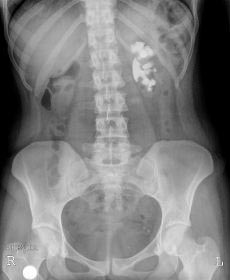

SIGNO VESICAL

Signo visible en la radiografía simple de abdomen que permite diferenciar entre una vejiga muy distendida (globo vesical) y una masa pélvica de otro origen. La distensión de la vejiga se ve como una densidad homogénea redondeada u oval de borde superior definido, que ocupa la pelvis obliterando las zonas laterales de la pelvis y desplazando lateralmente el ciego y el sigma.

Las flechas negras marcan el borde superior vesical bien definido. Obsérvese el borramiento de planos grasos en la pelvis (flecha naranja), el desplazamiento lateral del ciego (flecha blanca) y superior del sigma (flecha roja).